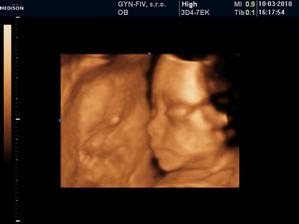

Ako rýchlo rastieme v brušinku 🙂

tatianka ďakujeme veľmi pekne 🙂 aj my sa z nich vytešujeme, kým je malinká v brušku a nevidím ju naživo